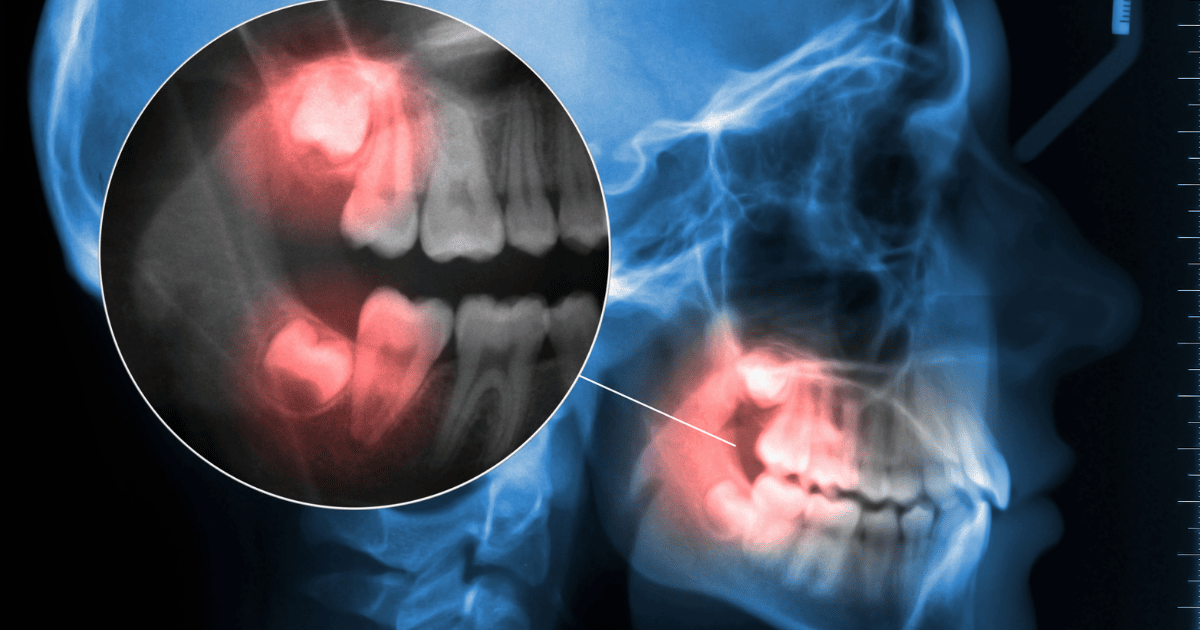

3日以上続く激しい痛み(ドライソケット含む)

抜歯後の痛みは2〜3日目にピークを迎え、徐々に引いていくのが一般的です。

しかし、3日以上経っても強い痛みが続く場合、「ドライソケット」の可能性があります。

ドライソケットとは、傷口を覆うはずの血の固まりが取れてしまい、骨がむき出しになっている状態です。

ズキズキと響くような鋭い痛みが特徴で、冷たい風や水にも敏感になります。こうした痛みがある場合は、すぐに歯科医院を受診してください。